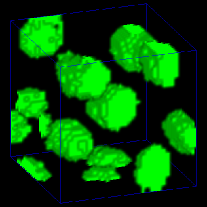

Our proposed method was compared to other 3D segmentation methods including 3D active surface [7], 3D active surface with inhomogeneity correction [8], 3D Squassh [9, 10], 3D encoder-decoder architecture [20], 3D encoder-decoder architecture with CycleGAN. Three original 3D subvolumes of Data-I were selected to evaluate the performance of our proposed method. We denote the original volume as subvolume (), subvolume (), and subvolume (), respectively. Corresponding groundtruth of each subvolume was hand segmented. Voxx [29] was used to visualize the segmentation results in 3D and compared to the manually annotated volumes. In Figure 5, 3D visualizations of the hand segmented subvolume and the corresponding segmentation results for various methods were presented. As seen from the 3D visualization in Figure 5, our proposed method shows the best performance among presented methods visually compared to hand segmented groundtruth volume. In general, our proposed method captures only nuclei structure whereas other presented methods falsely detect non-nuclei structures as nuclei. Note that segmentation results in Figure 5 yields smaller segmentation mask and suffered from location shift. Our proposed method shown in Figure 5 outperforms Figure 5 since our proposed method uses spatially constrained CycleGAN and takes consideration of the Dice loss and the binary cross-entropy loss.

To make this clear, segmentation results were color coded using 3D connected component labeling and overlaid on the original volumes. The method from [20] cannot distinguish between nuclei and non-nuclei structures including noise. This is especially recognizable from segmentation results of Data-I in which multiple nuclei and non-nuclei structures are colored with the same color. As can be observed from Figure 6 and 6, segmentation masks are smaller than nuclei size and suffered from location shifts. Conversely, our proposed method shown in Figure 6 and 6 segments nuclei with the right shape at the correct locations.